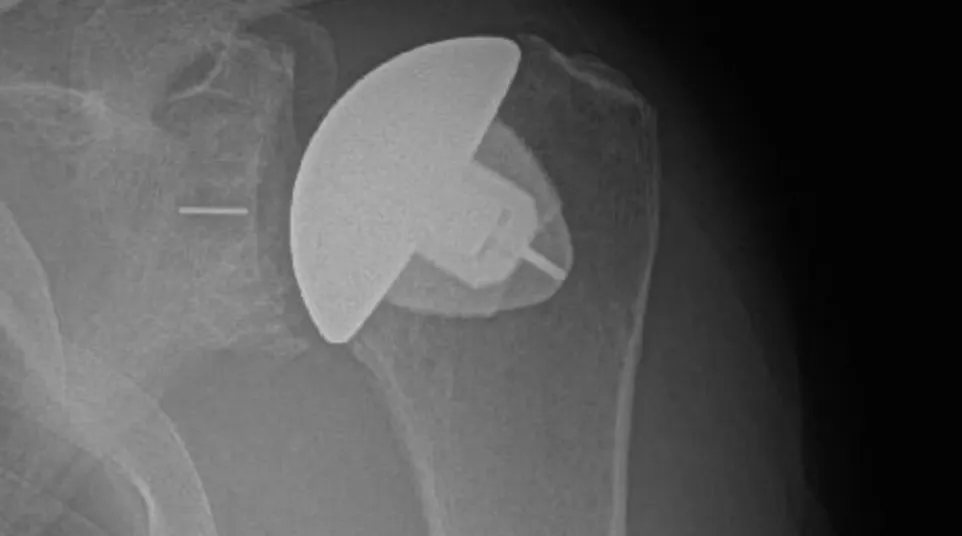

X-ray of shoulder showing a partial shoulder joint replacement implant inside the bone.

Partial Shoulder Replacement (Hemiarthroplasty):

In this procedure, only the ball of the joint is replaced with a prosthetic. It is generally recommended for patients with damage to the humeral head but a relatively healthy socket. Additionally, it is indicated for younger patients with high activity levels that put them at risk for loosening of the socket component. Hemiarthroplasty can also be utilized in cases of severe fractures.